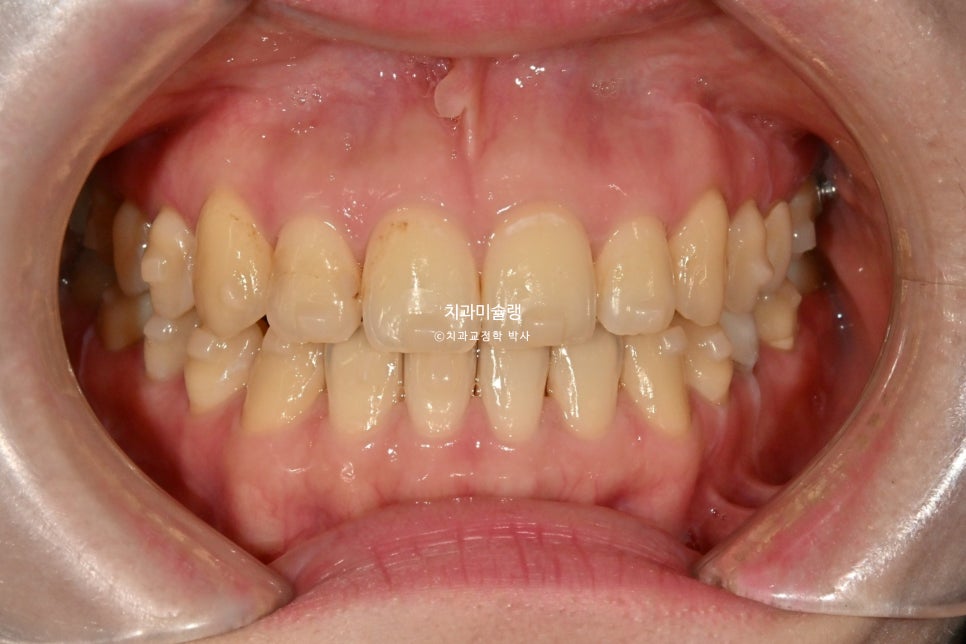

인비절라인 익스프레스 교정 결과

인비절라인 익스프레스로 작년 9월부터 2월까지 치료한 교정 결과를 한번 짚고 넘어가겠습니다.

중심선이 맞아졌으며 앞니 교합이 개선되었습니다. 기울어져있던 앞니 치축이 똑바로 개선되었습니다.

또한 내려와있고 튀어나와있던 송곳니는 제자리를 찾았습니다.

앞니 배열이 개선되면서 단차가 사라져, 이제는 삭제 없이 무삭제로 라미네이트가 가능합니다.